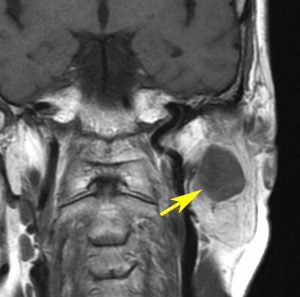

聴神経腫瘍や三叉神経鞘腫と間違えそうな顔面神経鞘腫

20代の男性で,下顎と口腔内の軽度の感覚以上だけがありました。聴力は正常で顔面神経麻痺は全くありません。でもこれは巨大な顔面神経鞘腫です。手術前は三叉神経鞘腫を疑っていました。

内耳道が少し拡大して内耳道内にも腫瘍があります。

手術摘出しましたが,聴神経は正常に見えて手術後も聴力は保たれました。三叉神経からは完全に剥離できています。

腫瘍の外側表面で顔面神経は紙のように薄くなって(菲薄化して),モニターで位置を確かめながらのかなり難しい手術となりました。